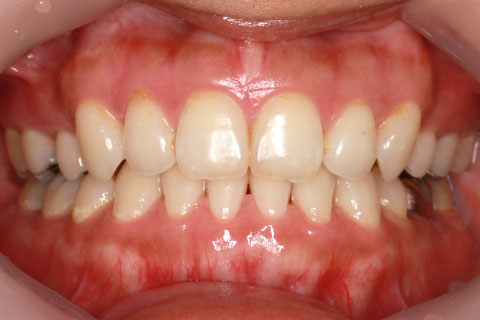

矯正期間18ヶ月

ハーフリンガル矯正2(上の歯のみ舌側矯正で治療)

治療前

治療中

治療後

- 年齢・性別

- 23歳女性

- 治療期間

- 1年6ヶ月

- 抜歯

- 上顎4番

- 治療費

- 110万円(税込み)

- 備考

- ハーフリンガル矯正

- 治療内容

- 上下前歯部凸凹の改善

- 施術の副作用(リスク)

- 裏側矯正の特性上、表側矯正と比較すると治療期間が長くかかる場合が多い。